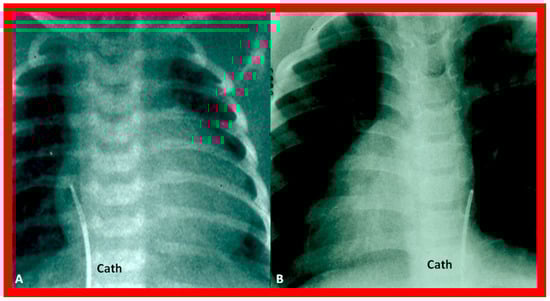

Figure 28. Cinefluoro images in posteroanterior views, illustrating positions of the catheters (Cath) in the inferior vena cava as they enter the right atrium (not labeled) in a patient with situs solitus (A) and another patient with situs inversus (B). Reproduced from reference [4].